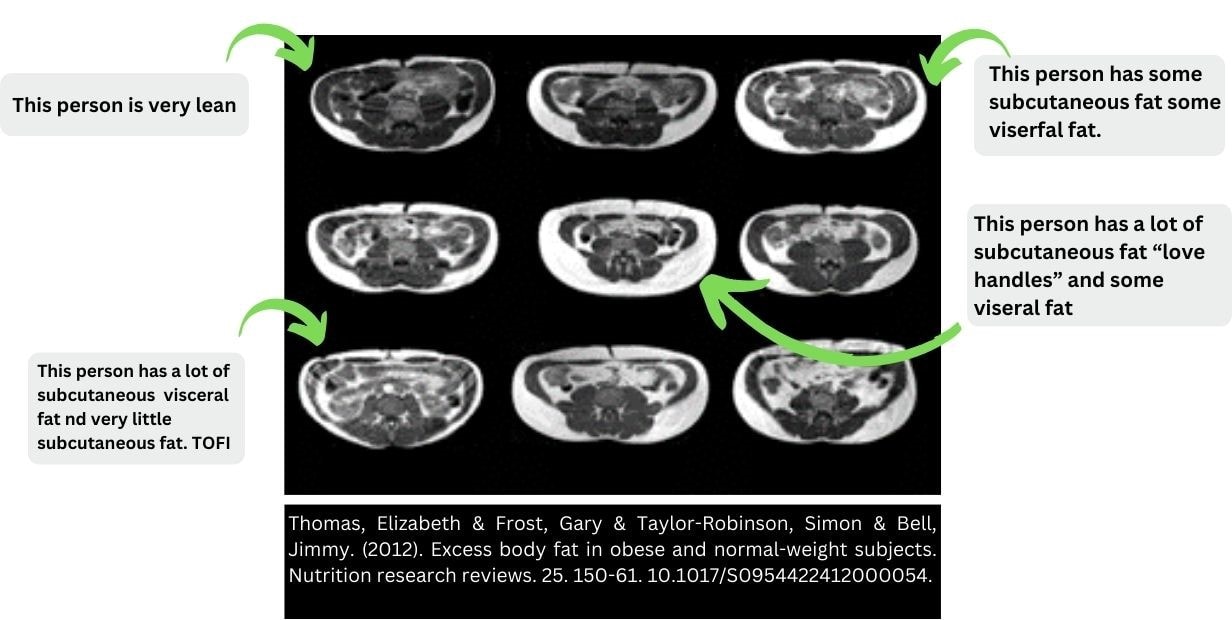

Thin Outside, Fat Inside (TOFI): Debunking Myths Surrounding Metabolic Health

Contrary to widely held belief, Metabolic Syndrome is not exclusive to visibly overweight individuals. The TOFI phenomenon occurs when individuals appear thin but harbor excessive visceral fat, highlighting the importance of considering diverse body types in diagnosis and prevention efforts. The individuals have a higher ratio of visceral to subcutaneous abdominal adipose tissue.